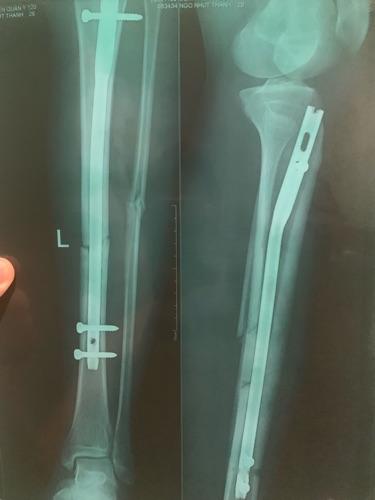

Chào bác sĩ, e phẩu thuật được 1 tháng 20 ngày, 2 phim này cách nhau 1 tháng, bá sĩ cho e hỏi với kết quả này có bình phục tốt không bác sĩ...e cần làm gì để bình phục tốt ạ...e cám ơn bác sĩ!

Chào e, phim e gửi sau điều trị đã bắt đầu hình thành can xương Cần 4-6 tháng để liền cứng E nên ăn uống tăng cường Calci và vitamin D kèm theo tập luyện vận động trị liệu PHCN để đạt KQ tốt nhất nhé